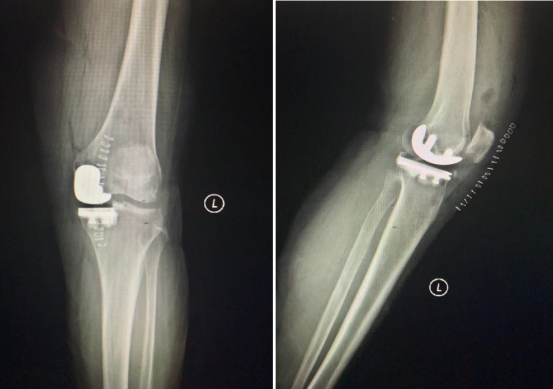

△术后